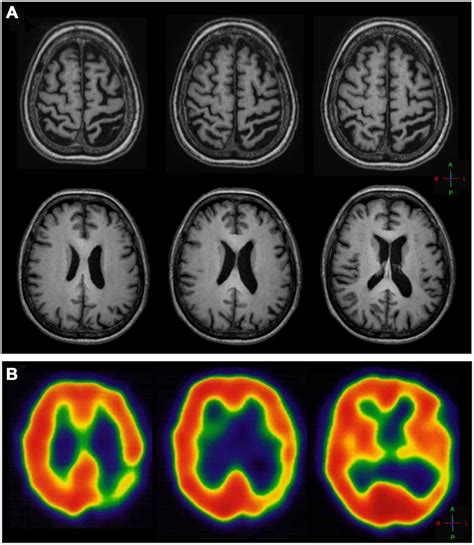

816×1203

pmc.ncbi.nlm.nih.gov

Alien hand sign or alien hand synd…